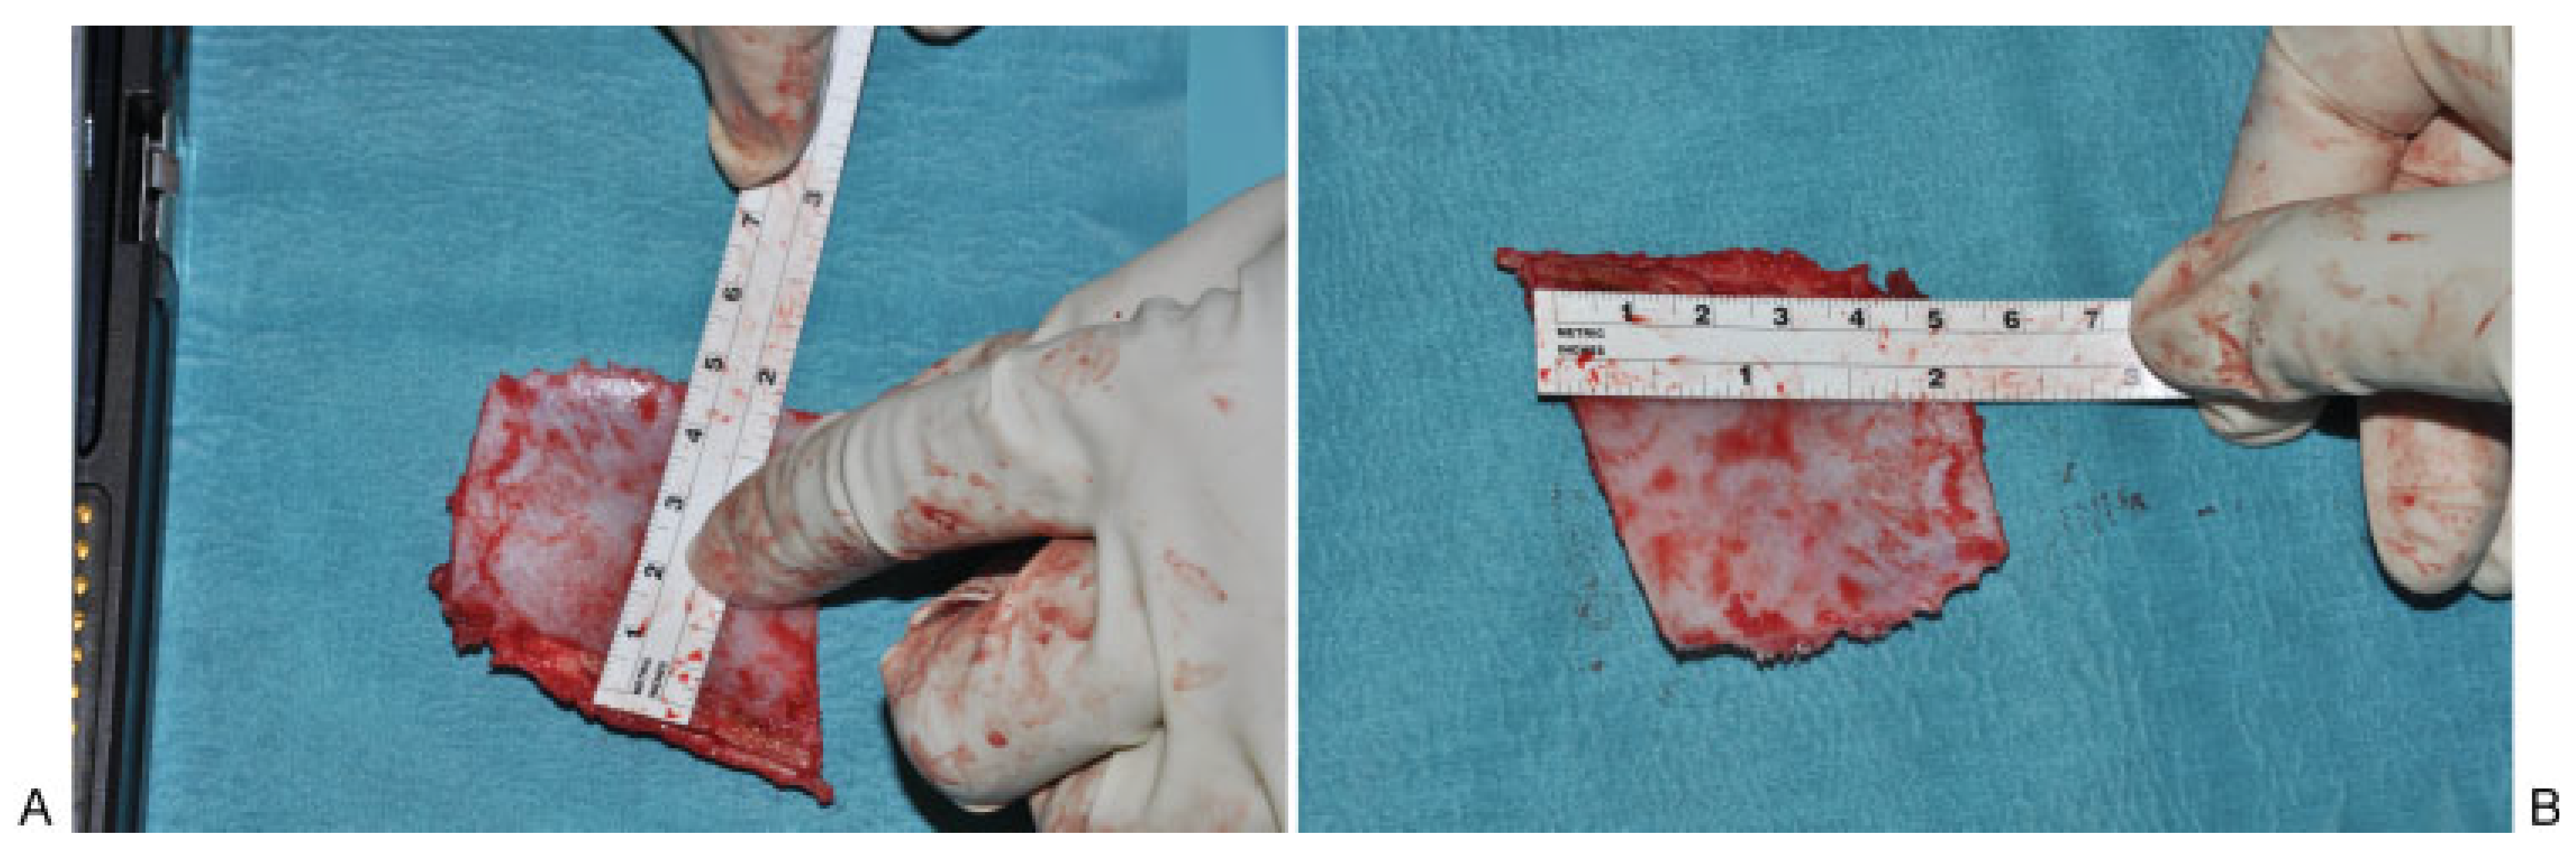

Surgical Technique